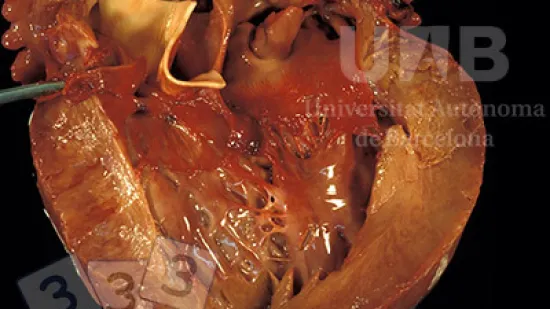

Wie nennt man die Veränderung bei diesem Herzen?